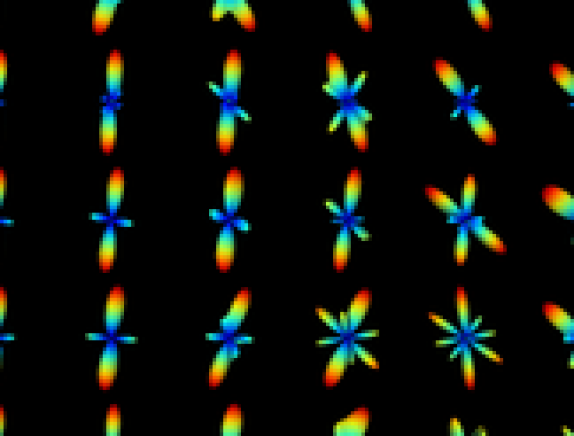

with the Gamma function and the modified Bessel function. Figure 1 shows some examples of the Kent distribution444Kent distribution has only one lobe. We added the antipodal symmetric lobe for visualization purposes. , given the parameters and .

| , | , | , |

![]() |